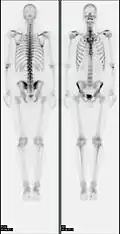

Nuklearne obrazowanie medyczne całego szkieletu. Badanie to wykonuje się gdy:

• podejrzenie nowotworu pierwotnego lub przerzutów do kości, a także ocenę skuteczności terapii,

• zapalenie kości i stawów,

• ocena zmian pourazowych,

• choroby metaboliczne kości.

Stosowany znacznik należy do grupy fosfonianów i jest transportowany za pomocą krwi. Wykazuje on naturalne gromadzenie się w strukturze kostnej – najbardziej intensywnie w kościach dobrze ukrwionych. W stanach chorobowych występuje zwiększenie aktywności procesów metabolicznych – gromadzi się więcej krwi niż w typowych warunkach[9][10]. Obrazowanie w takim przypadku ukazywałoby nadmierne nagromadzenie się znacznika badawczego. Stosuje się przede wszystkim znacznik 99mTc-MDP (metylenodifosfonian) o aktywności 550–750 MBq.